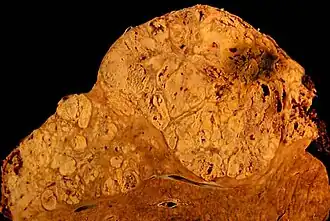

Indien men van leverkanker[1] of levercarcinoom[1] spreekt, bedoelt men een primaire kwaadaardige tumor, dat wil zeggen een kankergezwel dat in de lever zelf is ontstaan. In de Westerse wereld komt primaire leverkanker zelden voor, en is dan vaak veroorzaakt door alcoholmisbruik. In Afrika is dit type kanker echter een van de belangrijkste doodsoorzaken: het ontbreken van voldoende, hoogwaardige eiwitten in voedsel, de frequente besmettingen met hepatitis (vooral hepatitis B), en de inname van voedsel dat is bedorven door de schimmel Aspergillus flavus, die aflatoxine produceert, zouden daar debet aan zijn.

Tot de kwaadaardige of 'maligne', primaire levertumoren worden gerekend:

- cholangiocarcinoom: een tumor uitgaande van de galafvoergangen;

- hepatoblastoom: een levertumor vooral bij jonge kinderen;

- angiosarcoom: een tumor uitgaande van de bloedvaten;

- hepatocellulair carcinoom: tumor uitgaande van de levercellen